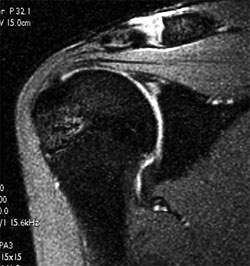

Μαγνιτική τομογραφία μιας βλάβης SLAP

στην γλήνη. Αυτή η πάθηση διαγιγνώσκεται ιδιαίτερα δύσκολα. Μόνο

η καλή κλινική εξέταση σε συνδυασμό με μια μαγνητική τομογραφία

με ενδοαρθρική έγχυση σκιαγραφικού οδηγεί με μεγάλο ποσοστό στην